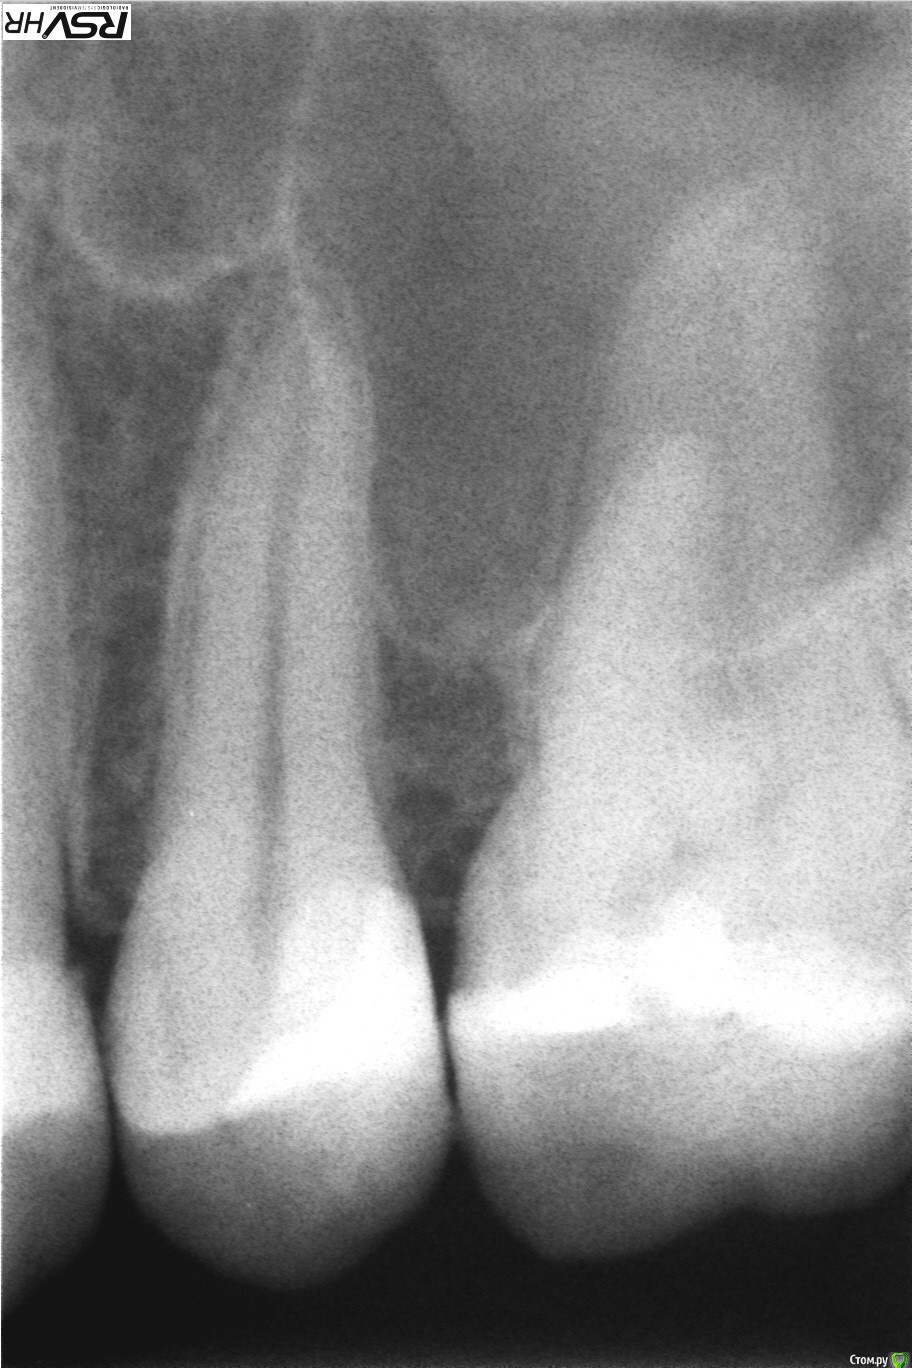

katrineigma Опубликовано 24 сентября, 2015 Поделиться Опубликовано 24 сентября, 2015 Была на приеме у стоматолога с пятым верхним зубом. Пришла вообще с другим, а этот и не беспокоил. Но сделали рентген и сказали надо удалять нерв. Потому что у этого зуба расширение периодонтальной щели, но пока не киста, как-то так, и если не пролечить сейчас, то потом вообще зуб придется удалять. Мне же зуб на снимке кажется абсолютно здоровым и теперь не дают покоя сомнения не зря ли мне удалили нерв. Прикрепляю рентген "До" и "После" лечения. Подскажите, действительно ли с зубом что-то не так? И заодно вопрос: канал запломбирован хорошо? Ссылка на комментарий

Romanson Опубликовано 24 сентября, 2015 Поделиться Опубликовано 24 сентября, 2015 Как давно ставили пломбу в этот зуб? Доктор, который депульпировал проводил какие-нибудь пробы для выявления живой нерв в зубе или нет (например, холодовую пробу)? После снятия старой пломбы доктор как-нибудь оценил состояние тканей под пломбой (был ли вторичный кариес под пломбой)? Слишком мало данных для того, чтобы делать какой-то вывод. Но, если интересно частное мнение, то если бы ко мне пришел пациент с таким зубом, и тесты на витальность оказались положительными (т.е. зуб реагировал как-нибудь на раздражители, например на холод, как здоровый зуб) я бы предложил за таким зубом понаблюдать (прийти через пол года, повторно сделать снимок и провести пробы). Канал запломбирован нормально. Ссылка на комментарий

katrineigma Опубликовано 24 сентября, 2015 Автор Поделиться Опубликовано 24 сентября, 2015 Как давно ставили пломбу в этот зуб? Доктор, который депульпировал проводил какие-нибудь пробы для выявления живой нерв в зубе или нет (например, холодовую пробу)? После снятия старой пломбы доктор как-нибудь оценил состояние тканей под пломбой (был ли вторичный кариес под пломбой)? Слишком мало данных для того, чтобы делать какой-то вывод. Но, если интересно частное мнение, то если бы ко мне пришел пациент с таким зубом, и тесты на витальность оказались положительными (т.е. зуб реагировал как-нибудь на раздражители, например на холод, как здоровый зуб) я бы предложил за таким зубом понаблюдать (прийти через пол года, повторно сделать снимок и провести пробы). Канал запломбирован нормально.Пломба, которая на первом снимке, была поставлена года 4 назад, а депульпировали зуб на днях. Проб никаких не проводили...После снятия пломбы уже не было комментариев, решение об удалении нервов было принято по рентгену еще до снятия пломбы, потому и возник вопрос, действительно по рентгену что-то видно, какие-то патологии? Ссылка на комментарий

katrineigma Опубликовано 25 сентября, 2015 Автор Поделиться Опубликовано 25 сентября, 2015 Не совсем понял. Вас беспокоил другой зуб, а патологию доктор нашел в этом? Так было? Если так, то определить, сделано ли все правильно, очень просто по отсутствию жалоб после лечения...Зуб беспокоил соседний, шестой, но тоже не болел, просто видно было, что там кариес и надо лечить, однако врач обратил внимание в первую очередь на пятый зуб, сказав, что он скорее всего мертвый, так как на нем очень большая пломба, послал на рентген пятого зуба, чтобы убедиться, что он всё-таки живой, и по рентгену же сказал, что надо удалять нервы. Сейчас вопрос даже не столько в том, правильно ли был запломбированы каналы, сколько в том, стоило ли их вообще пломбировать и убивать нервы пытаюсь понять действительно ли на рентгене что-то не так и что именно Ссылка на комментарий

katrineigma Опубликовано 27 сентября, 2015 Автор Поделиться Опубликовано 27 сентября, 2015 То есть только рентген? Никаких тестов в клинике не было вобще? Не стучали ничем по зубу тоже?Нет, ничем не стучали и тестов никаких не было...врач еще до рентгена сказал, что зуб скорее всего мертвый, на что я сказала, что он точно живой, врач удивился: "Такая огромная пломба и живой?", послали на рентген удостовериться,и, собственно вот....на рентгене, значит, все нормально и мои опасения, что зря нервы удалили, оправдались? Ссылка на комментарий

St. Опубликовано 27 сентября, 2015 Поделиться Опубликовано 27 сентября, 2015 Ну почти... По рентгену можно заподозрить проблему, не более. Окончательно сказать можно только после мероприятий описанных выше. Ссылка на комментарий